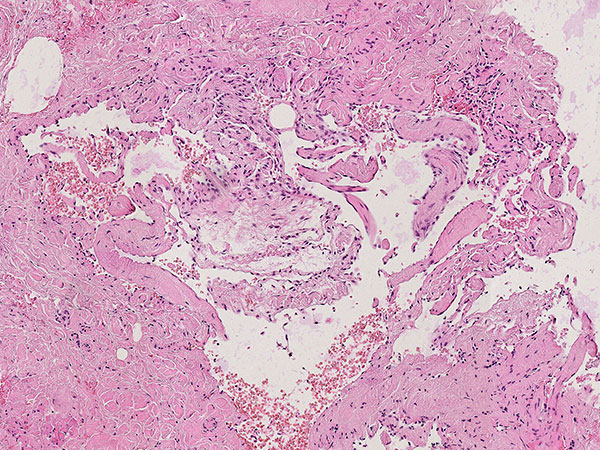

Hämatoxylin-Eosin-Färbung, 64-fache Vergrößerung: Schichtartiger, vor allem zentral vorwiegend bindegewebiger Aufbau des bereits älteren, teilorganisierten Phlebolithen. Umgeben wird der Phlebolith von multiplen vermehrten, irregular aufgebauten, dünnwandigen Gefäßräumen.